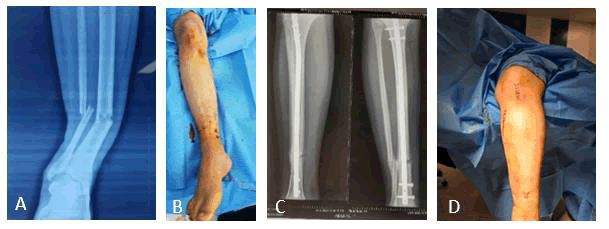

Patients in the supine position, draping done, the leg rested on a radiolucent sterile frame (plastic or wooden) knee flexed 45°, or the leg hang over the operating table (90° knee flexion). Three cm incision (from the lower pole of the patella to tibia tuberosity), then passing medial to or through the patellar tendon. Then the guide wire anterior to the tibial spine (eminence) as a pilot hole under fluoroscopy image intensification both anteroposterior and lateral view to guarantee the proper site of entrance for the subsequent steps; introducing the awl then the ball-tipped guide wire to continue the steps of reduction then reaming of the intramedullary canal. The reaming started with the smallest reamer size to reach the optimum size of reaming in a step manner, then choosing an intramedullary nail 1 cm smaller than the last reamer size. Further check for the nail size and length was also done, introducing the nail smoothly into the bone. Distal locking screws tightened (either freehand or with the assistance of a locking device). The fracture was checked with imaging about the reduction (which sometimes required a step of fracture impaction when there is displacement). Proximal screws then tightened. Closure in layers of the main incision skin and other punctures closed with a stapler (Figure 3).

Fig. 3. A) Radiograph showing fracture lower shaft of right tibia. B) 3 cm anterior right knee incision (lower pole of patella to tibial tuberosity) with proximal and distal 2 x 2 punctures for insertion of derotation locked screws. C) Postoperative radiograph AP and lateral. D) The way of hanging the leg on the regular operating table.